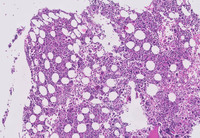

Figure 2: Images of bone marrow core biopsy in CML–accelerated phase

Low power image demonstrating markedly hypercellular marrow with significantly increased numbers of megakaryocytes visualized at higher power.  The image at the bottom depicts numerous megakaryocytes that comprise an admixture of dwarf forms with hypolobated nuclei (typical in CML) as well as forms comprising micromegakaryocytes with dysplastic features.  The background comprised and equal admixture of maturing myeloid and erythroid precursors without the typical myelocyte bulge seen in chronic myeloid leukemia, chronic phase.